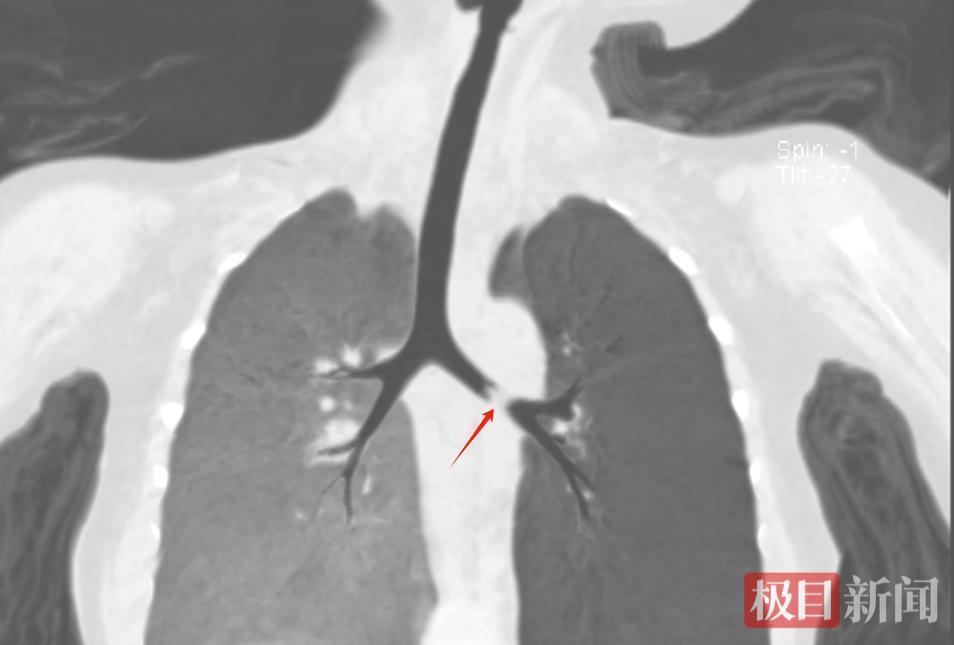

该院门诊以“急性喘息性支气管炎、支气管异物”将瑞瑞收入院。复查肺部CT提示,异物卡在了左侧支气管。情况紧急,该院耳鼻咽喉科医生迅速为其进行了全麻下气管镜支气管异物取出术。

图片堵在气道里的异物

孩子因为气道被异物堵塞,造成呼吸道梗阻。术中,专家需要经口行气管镜检查,这一操作有可能加重堵塞,因此手术对麻醉、手术医生救治能力要求很高。在耳鼻咽喉科、麻醉科、手术室团队协作下,有惊无险地取出了一块坚果。